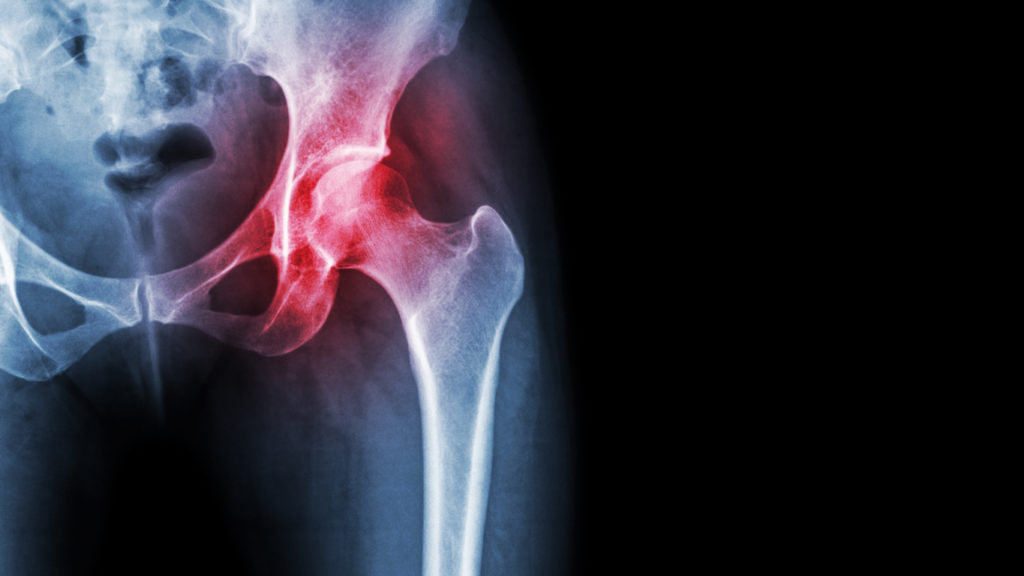

If noninvasive treatments and joint-injection treatments have not worked to provide lasting relief from your arthritis pain, your orthopedic surgeon may recommend a surgical approach. This may be total joint replacement, partial joint replacement, or joint resurfacing surgery.

A joint replacement involves replacing the joint with an artificial (prosthetic) one. This is most commonly done in a hip or knee.